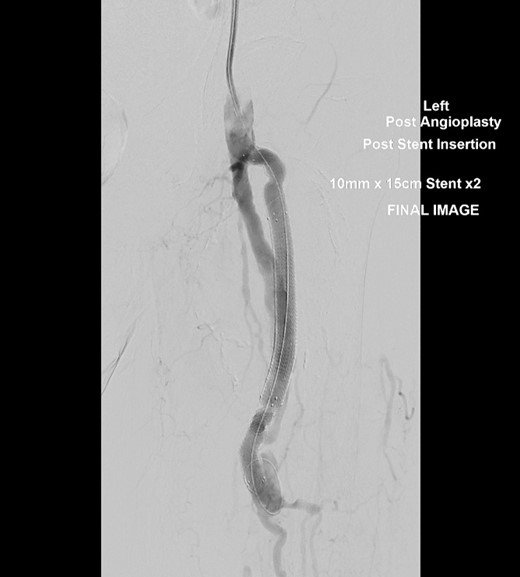

Conventional angiogram of the left PFA was performed under local anaesthetic. Ultrasound guided puncture of the left common femoral artery was performed and two 10 mm × 150 mm Viabahn stents were placed via an 8 French sheath. Aneurysm exclusion was achieved as seen in Fig. 2 and flow is seen in the distal PFA. Stent patency was further confirmed post procedure using an Ultrasound Doppler.

Conventional angiogram of the left PFA showing exclusion of the aneurysm and flow into the distal PFA after deployment of a second 10 mm × 150 mm Viabahn stent.